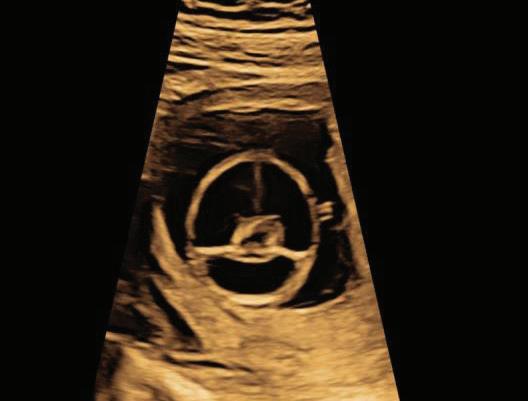

The first trimester— spanning from conception to 13+6 weeks—is no longer considered a “blind phase” of pregnancy. With the evolution of highresolution ultrasound, color Doppler and advanced biochemical screening, this period has transformed into a window of opportunity for early fetal evaluation, risk prediction and preventive strategies.

First-trimester fetal evaluation is not limited to dating the pregnancy or confirming viability—it is the foundation of predictive, preventive, and personalized obstetric care.

2. NUCHAL TRANSLUCENCY (NT) SCAN

• Done @11–13+6 weeks.

• CRL 45–84 mm.

• This is the cornerstone of first trimester screening.

1. NT is the sonographic appearance of subcutaneous accumulation of fluid behind the fetal neck, below the skin in the first trimester of pregnancy.

2. Measured in mid-saggital section only.

3. Measured between 11-14 weeks.

4. CRL between 45-84mm.

5. Magnified to include only head and upper thorax.

6. Fetus should be in neutral position.

7. Demostrate fetus separate from amnion.

8. Measurement should be ON to ON (cross bar of the callipers should be such that it’s hardly visible and merges with white line, not nuchal fluid).

During the scan more than one measurement should be taken and maximum value should be considered.